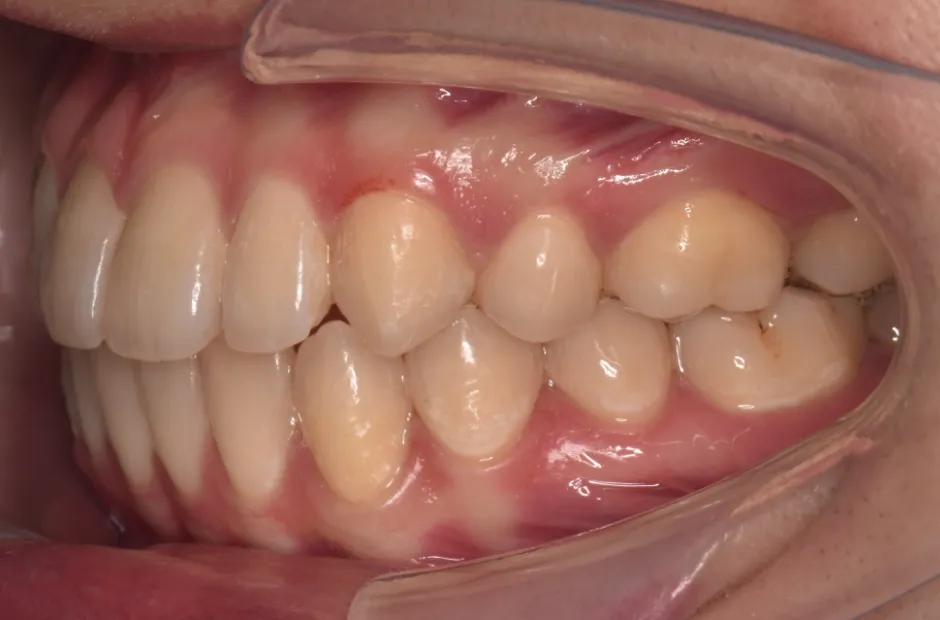

叢生

| 診断名・主訴 | 叢生 |

|---|---|

| 年齢・性別 | 43歳・女性 |

| 治療期間・回数 | 2年7か月 27回 |

| 治療に用いた主な装置 | 舌側矯正 |

| 抜歯部位 | 両顎4,4 |

| 治療費 | 100万円(税抜) |

| リスク・副作用 | 装置による違和感・疼痛・歯肉退縮・歯根吸収・虫歯のリスクなど |

治療前

治療中

治療後